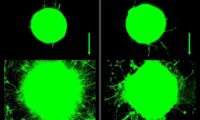

【大紀元日本9月26日】最近の医学の研究結果によれば、母の愛はただ感情の感受だけでなく、子供の大脳の構造を変える力を持ち、より多く母の愛情を受けた子供は大脳の海馬がより大きいという。海馬は大脳の重要な部分であり、学習や記憶、行動が密接に関係している。

ワシントン大学のジョアン・ルビ博士の研究チームは一連の実験研究を行ない、脳の海馬の大きさは幼児時期に受けた愛情に関係し、より多くの関心と愛情を受けた子供はその海馬がより大きい。また、成長してから、学業、仕事及び社交において関心と愛情をあまり受けてない子供より、優秀な表現が現れることが分かった。この研究結果は「米国国家科学院雑誌」に発表された。

一方、カナダのマギル大学神経学のマイケル・ミニー教授の研究チームは動物(マウス)実験で研究した結果、母の愛情は子供の大脳の遺伝子発現を改変できることが分かった。しかもこのような遺伝子発現の改変は持続的なもので、次世代に遺伝し、大脳の海馬の部分により多くのストレス受容体を形成する。そこで身体のストレスに対する障害が軽減し、子供はよりのびのびと成長できる。